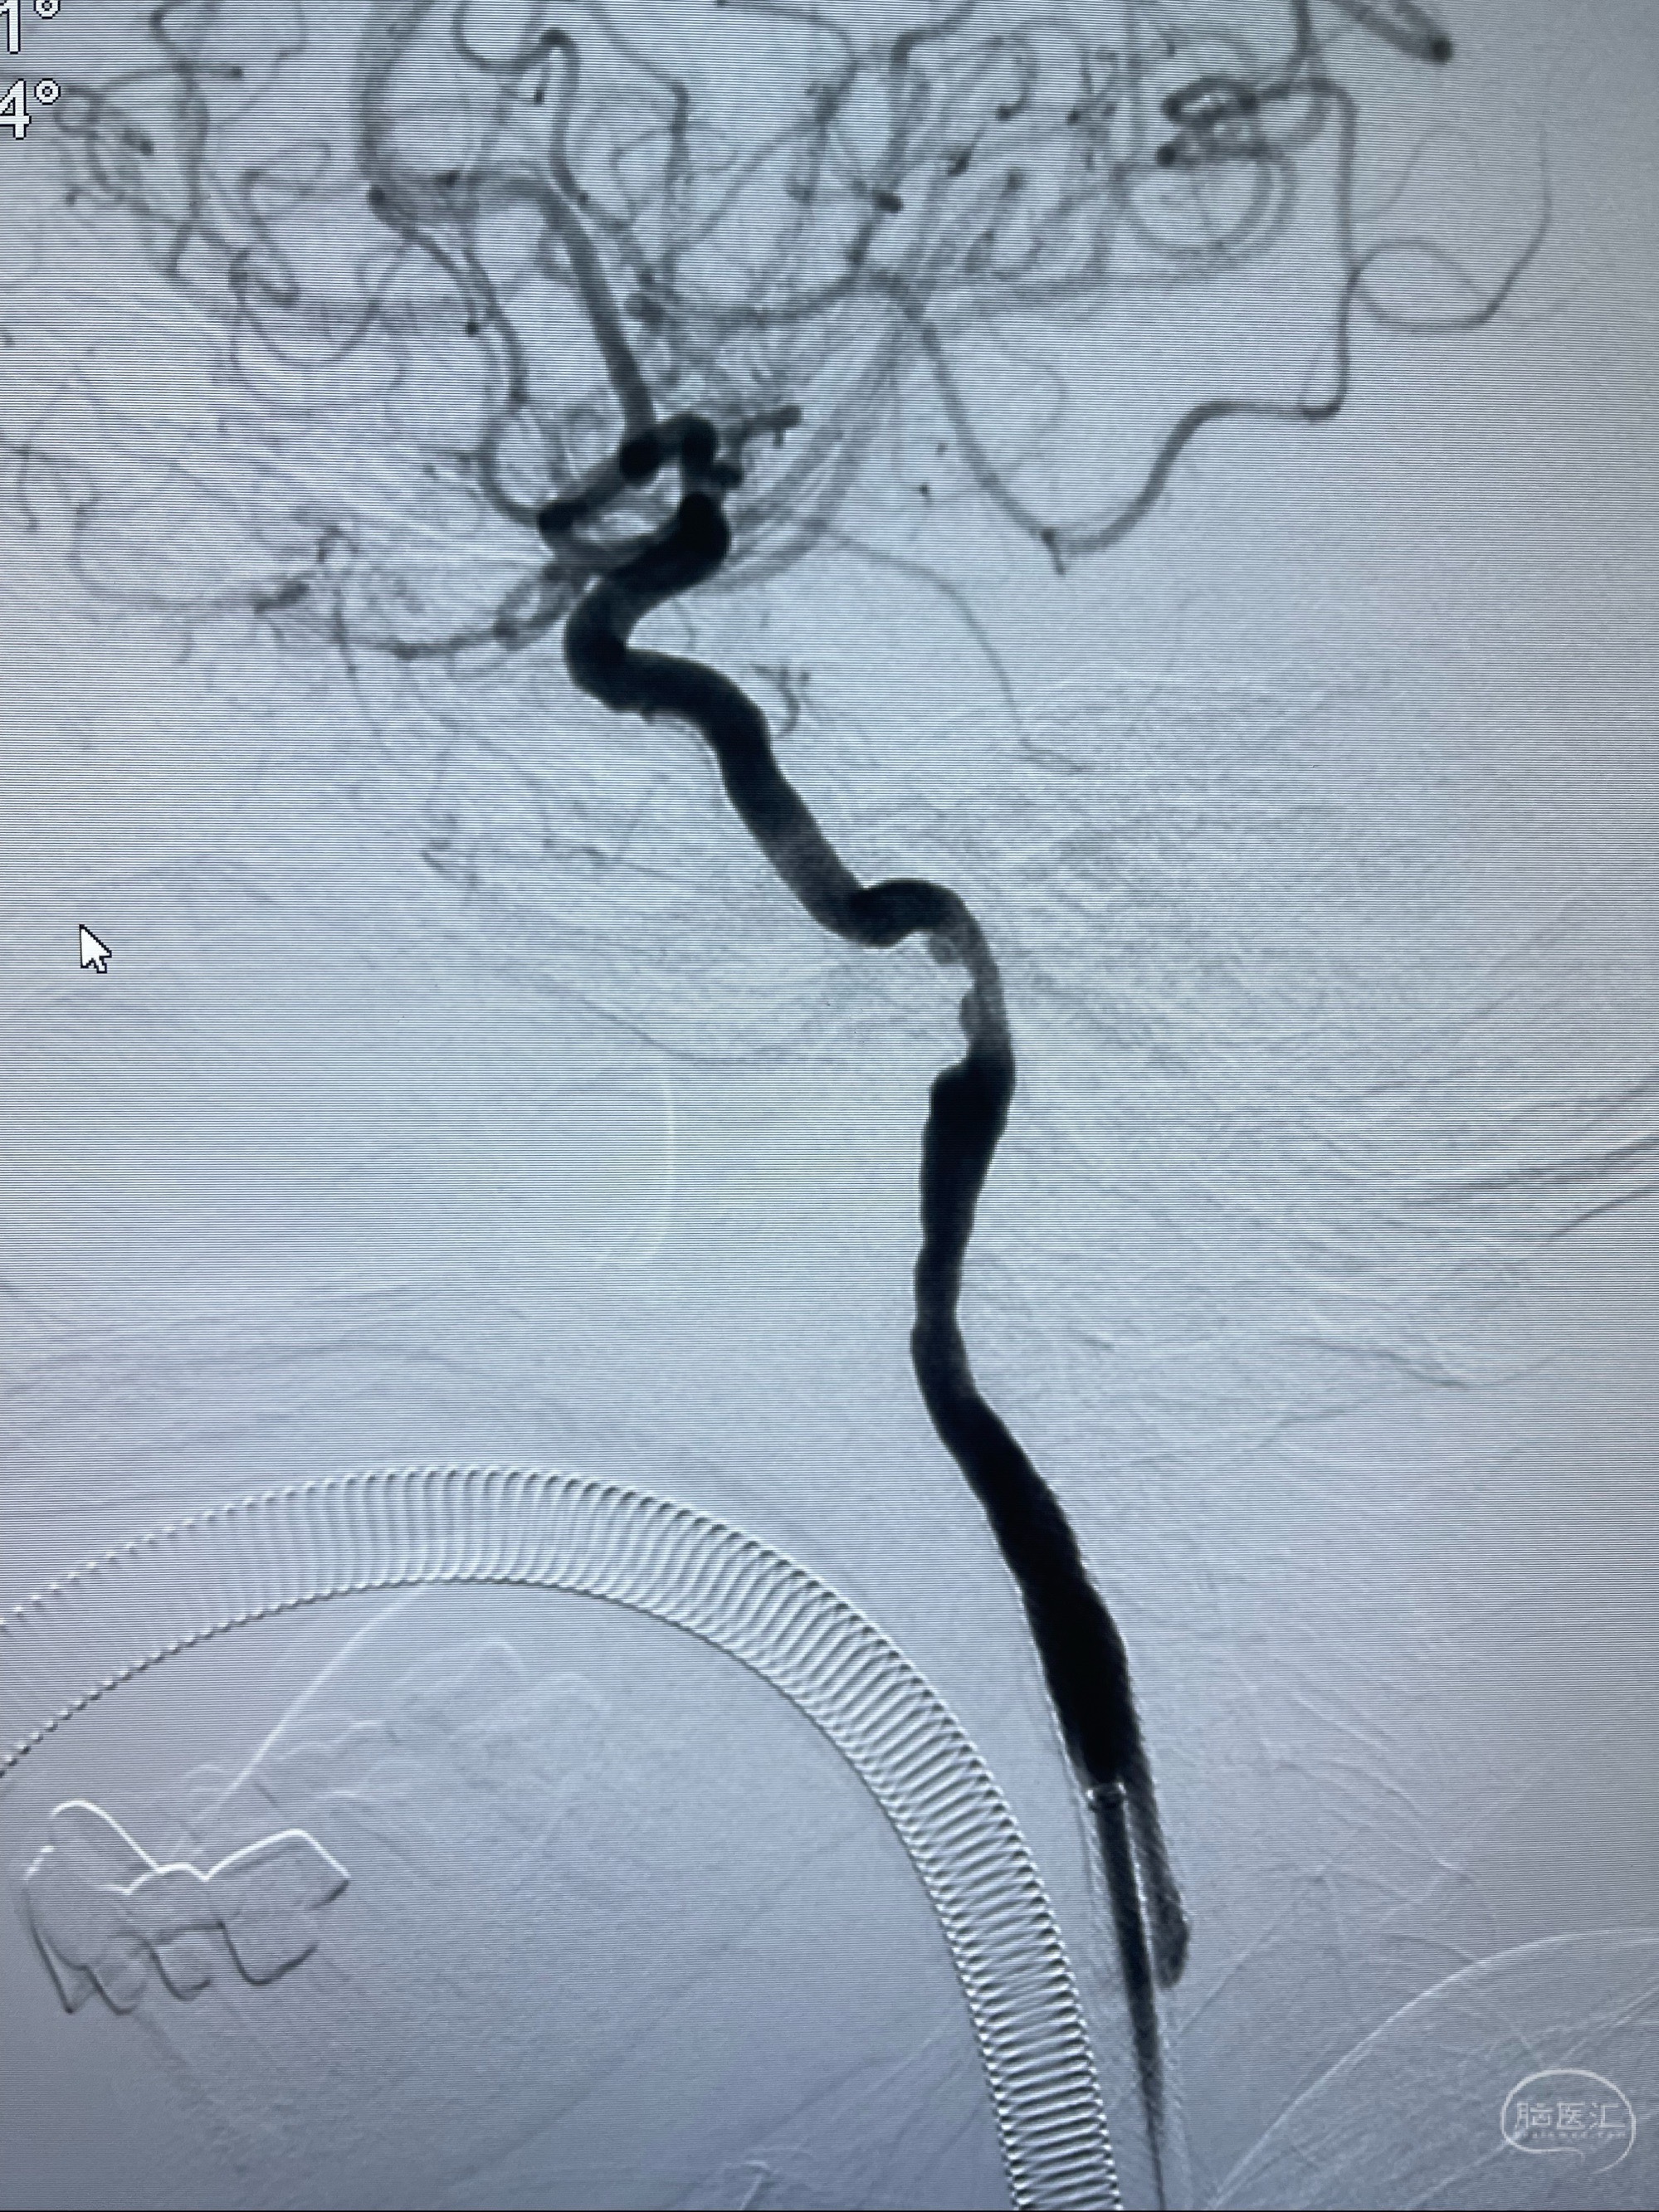

2023-07-10DSA:右侧颈内动脉岩骨段夹层伴中偏重度狭窄改变,左侧颈总动脉闭塞、右侧颈外动脉由右侧肋颈干甲颈干吻合代偿

箭头所示为颈内动脉岩骨段重度狭窄,结合MRI,考虑为肿瘤侵犯右侧颈内动脉

箭头以近至支架段管腔不规则狭窄

088NeuroMAX100cm长鞘在125cmMPA及黑泥鳅导丝引导下超选择性插入右侧颈内动脉支架内

经导引导管造影显示支架远端颈内动脉不规则狭窄伴局部充盈缺损,同时行全身肝素化5ml